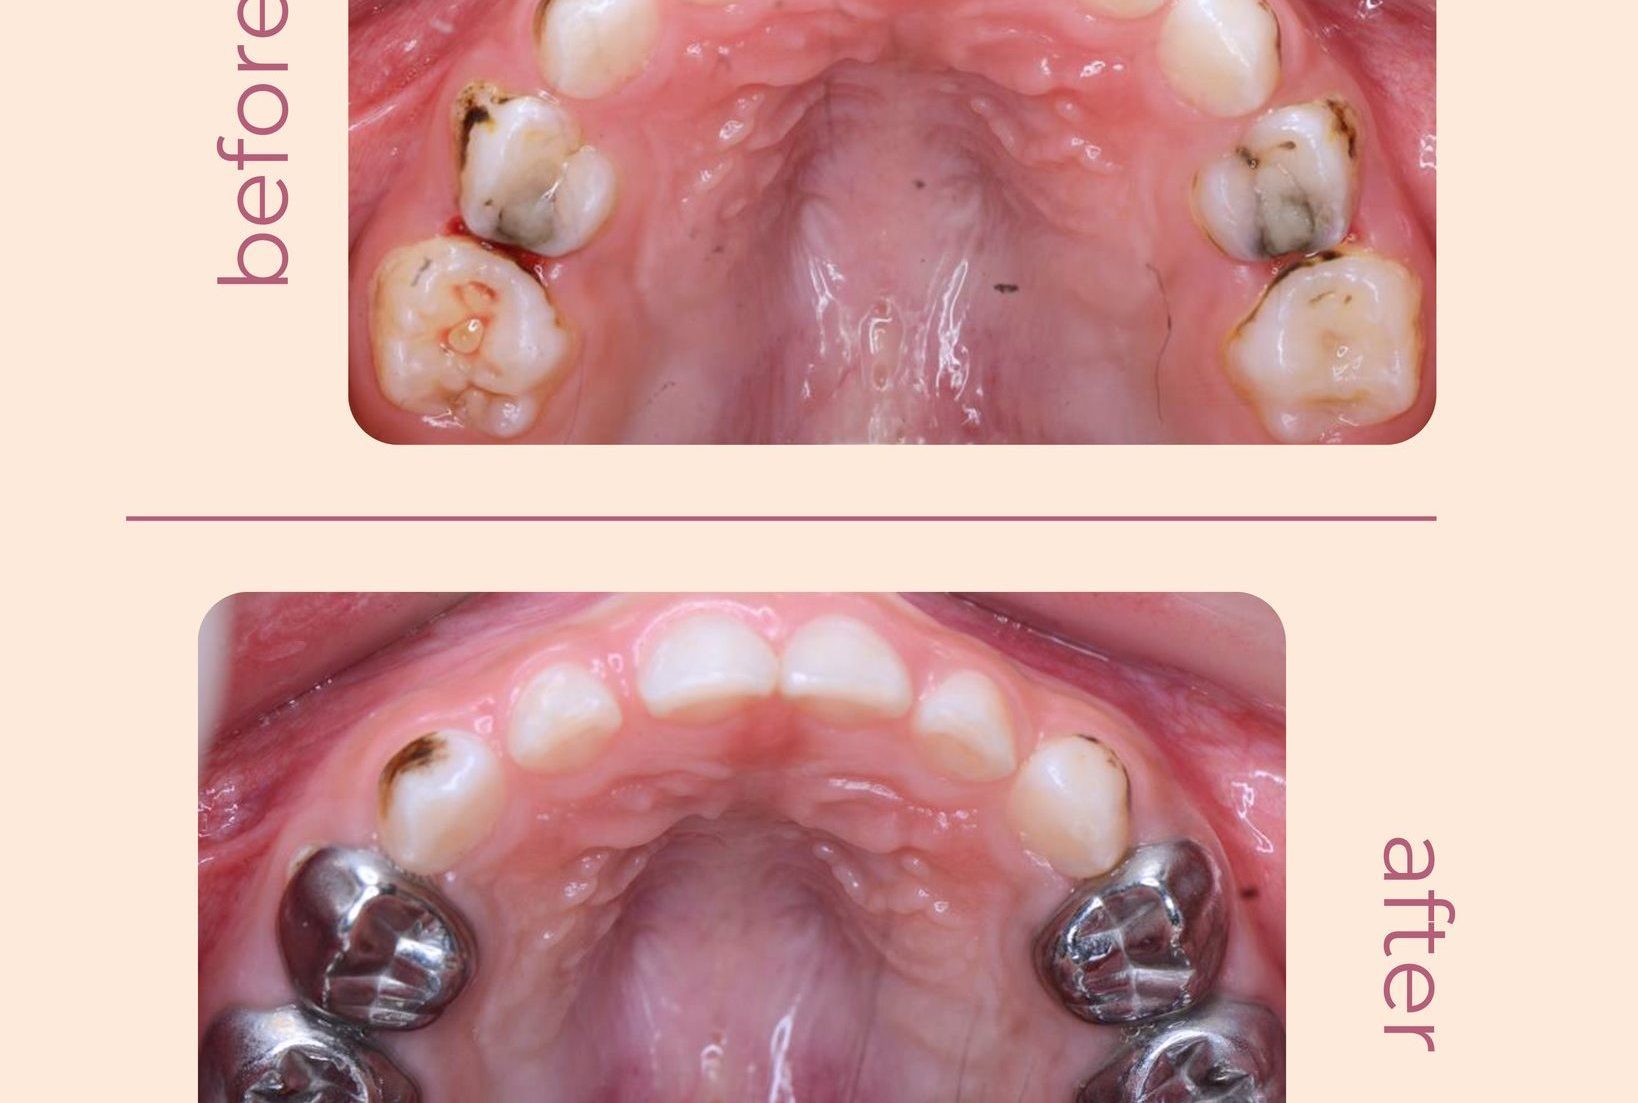

Hình Ảnh Trước & Sau Điều Trị

Minh chứng rõ ràng cho chất lượng và hiệu quả tại Nha khoa Như Ngọc – nơi mỗi khách hàng đều tìm lại được nụ cười tự tin sau quá trình điều trị và thẩm mỹ răng